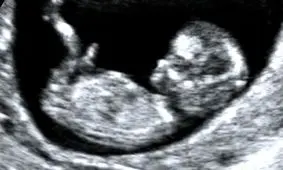

پزشکان نخستین سونوگرافی از جنین را در زنان باردار بین هفتههای ۹ام تا ۱۲ام انجام میدهند که از طریق آن میتوان موارد…